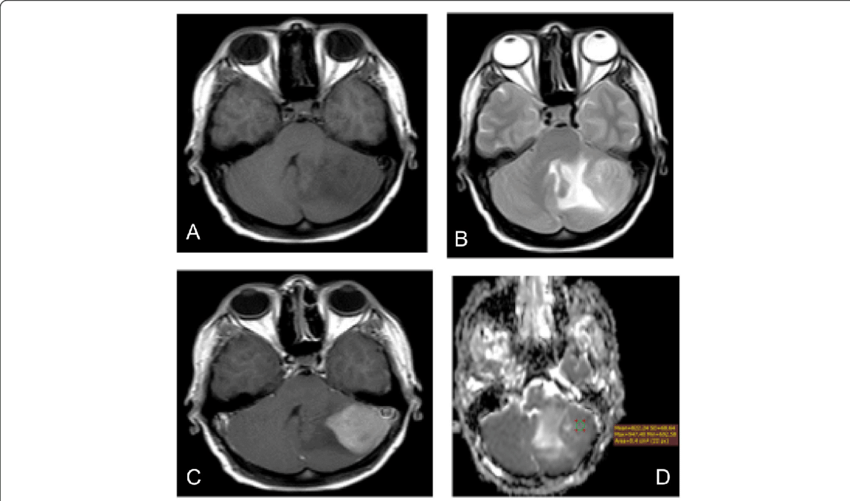

At Indotaj Medical Center in Tajikistan, a meningioma refers to a tumor originating from the meninges, which are the protective layers covering the brain and spinal cord. These tumors arise from arachnoid cells, located within the delicate, web-like membrane forming one of the three layers of the meninges.

• Ensure that any necessary diagnostic imaging studies, such as MRI or CT scans, are completed before the consultation.